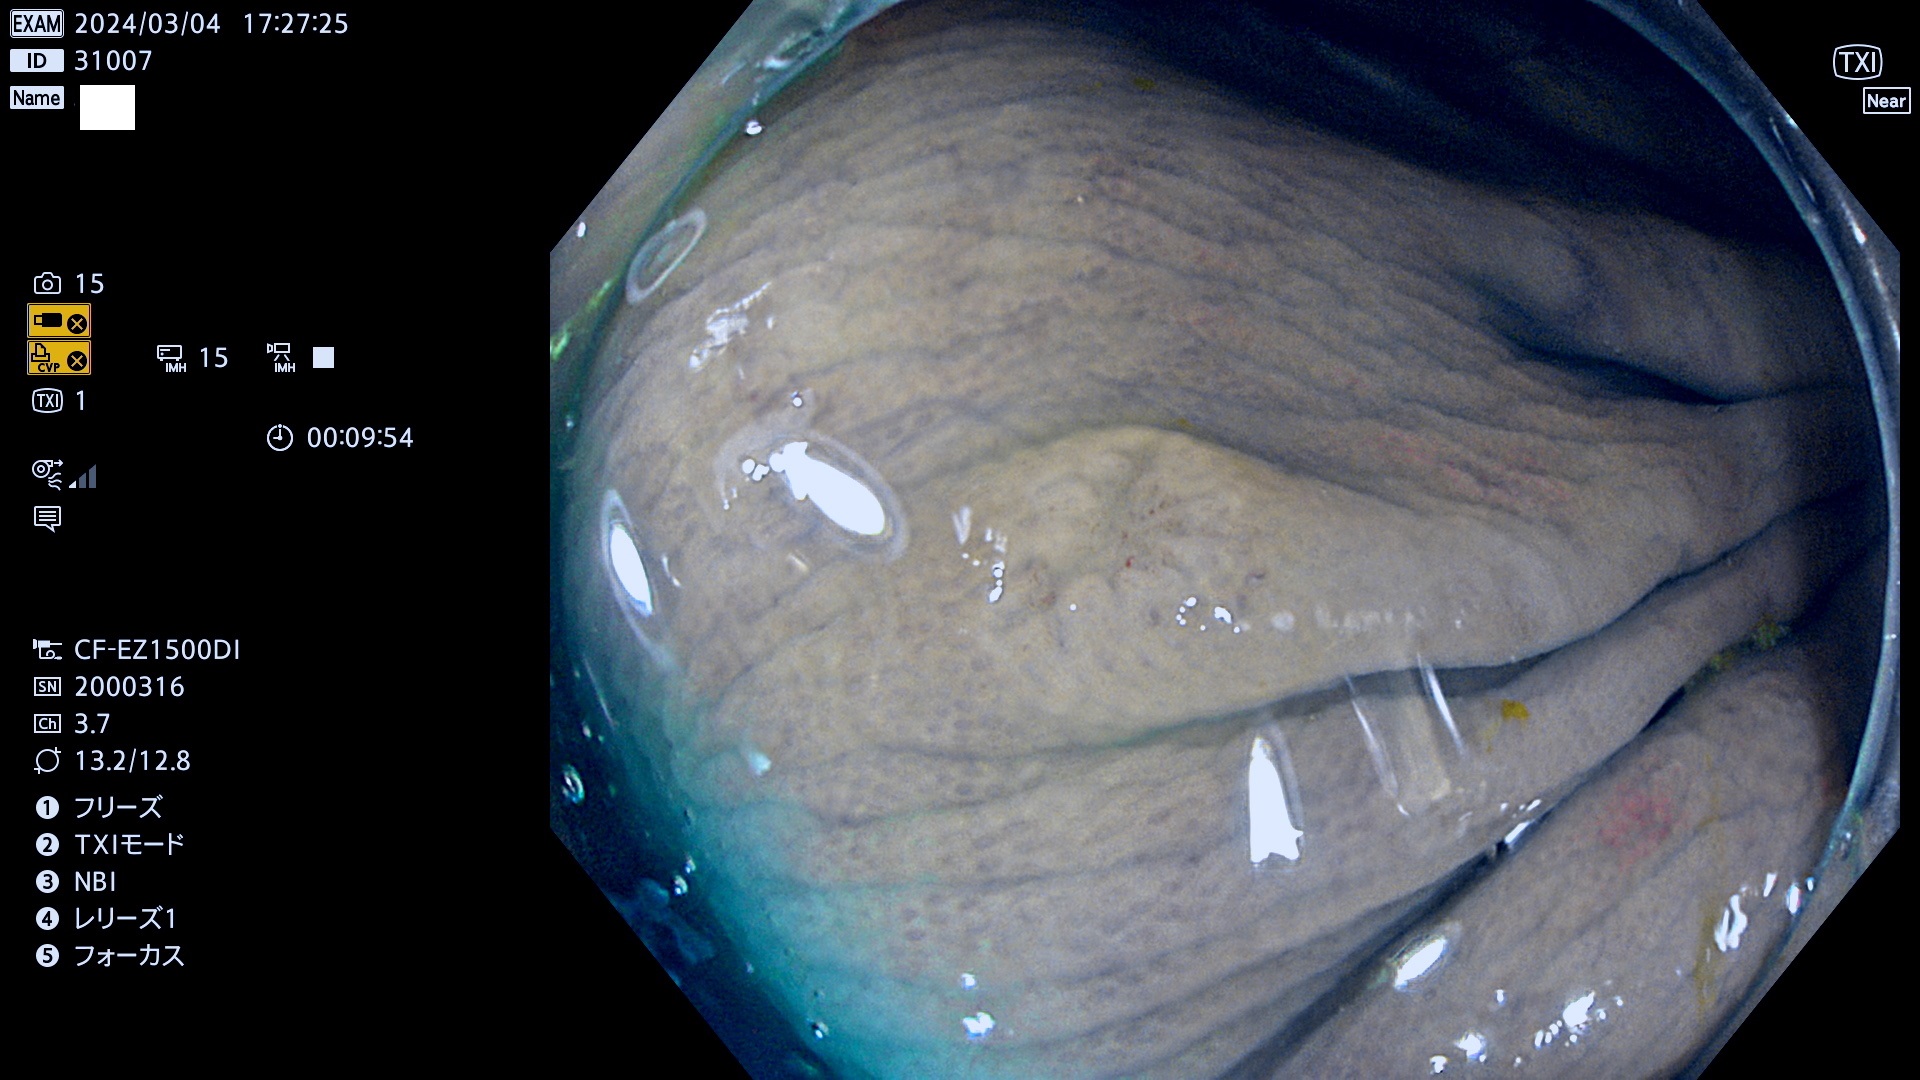

表面型腺腫(Flat Adenoma)の中で、完全に平坦な物をUb、陥凹している物をUcと呼びます。平坦隆起型(Ua)よりも、発見が難しく危険な病変です。

専門的)Uc=De Novo癌? 内視鏡の解像度が低かった時代、このような説もありました。しかし今日の高精度内視鏡では良性の微小なUc型腺腫が日常的に見つかります。私見ですが「Ucこそが多段階発癌(Adenoma-Carcinoma Sequence)のMain Route」と考えます。

毎週の検査(木・金・土・日)に発見されたUb、Uc型・腺腫を、その週の日曜の夜にUPし1週間、提示します。

抽出の対象期間 2024年2月29日(木)〜3月4(日)の5日間(50件の検査)4件 (4/50=8%)